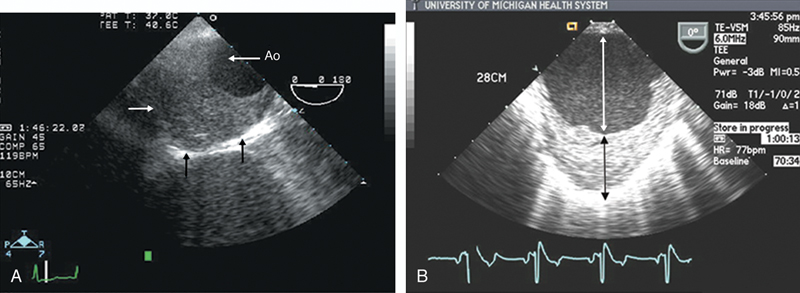

فحوصات تشخيصية لبعض امراض القلب والشرايين التاجية